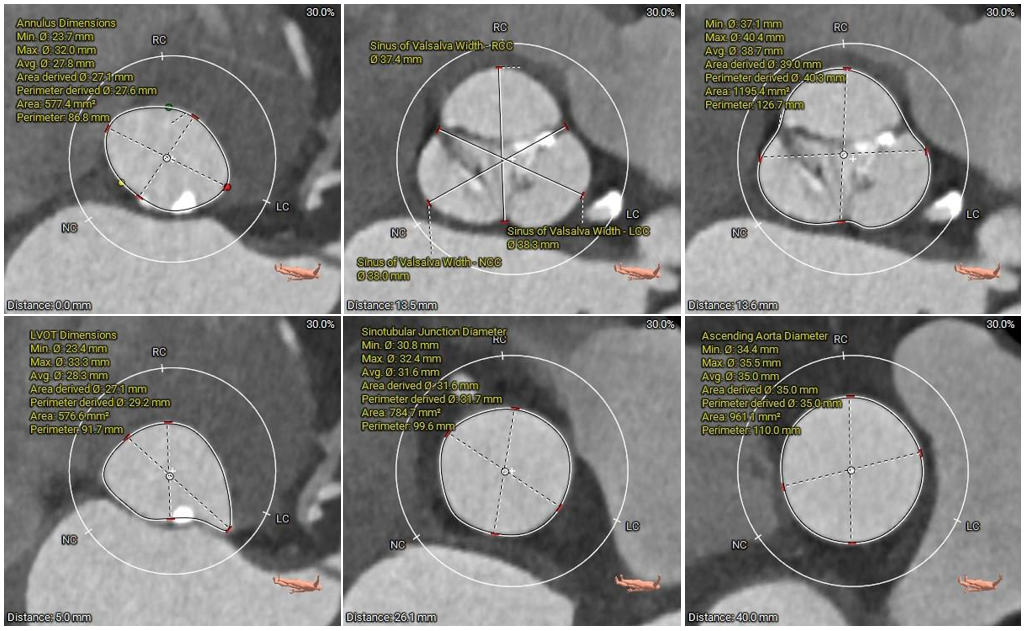

术前CT评估:

本例患者为主动脉瓣重度狭窄伴中度反流,因反复严重心衰伴心绞痛多次住院,同时合并高血压病、陈旧性脑梗死等基础疾病,一般状况不佳,无法耐受外科开胸手术,有强烈的微创换瓣手术意愿;患者术前心脏彩超、CT等评估适宜行TAVR手术,TAVR手术指征明确。CT分析提示患者为Type1型二叶式主动脉瓣,瓣叶明显增厚伴重度钙化,左右窦间可见钙化融合嵴,瓣膜植入后受钙化嵴挤压影响存在瓣周漏风险;此外,患者左窦间存在长条状钙化延伸至瓣环下10mm水平,瓣膜植入后可能压迫传导束,存在起搏器植入风险,对瓣膜释放位置及精准度要求较高,需要术者快速、精准的操作能力及手术团队的密切配合。

手术过程中,在完成跨瓣操作后,23mm球囊预扩有轻微腰征、无造影剂渗漏,预装TaurusElite AV29瓣膜到位,输送系统快速、顺利地完成过弓、跨瓣操作,于瓣环上约2mm定位释放;针对本例患者瓣叶明显增厚伴重度钙化,左右窦间可见钙化融合嵴的特点,TaurusElite瓣膜高密度流入端设计提供了足够的径向支撑力,保证了瓣膜的锚定力,瓣膜内外双裙边设计能提供良好的辅助锚定力,有效减少瓣周漏。此外,本例患者左窦间存在长条状钙化延伸至瓣环下10mm水平,释放位置偏深可能存在起搏器植入风险,TaurusElite瓣膜具有多次完全可回收,回收后可重新跨瓣、释放的特点,给予术者足够的信心完成高位释放的操作,释放后最终瓣架底端位于瓣环下约1mm,实现了释放位置的精准控制,有效的减少了起搏器植入风险,确保了手术安全、顺利的完成。这例手术为永州地区开展的第一台TAVR手术,填补了该地区TAVR技术空白,标志着永州市心脏瓣膜疾病诊治迈入了全新的微创治疗时代!